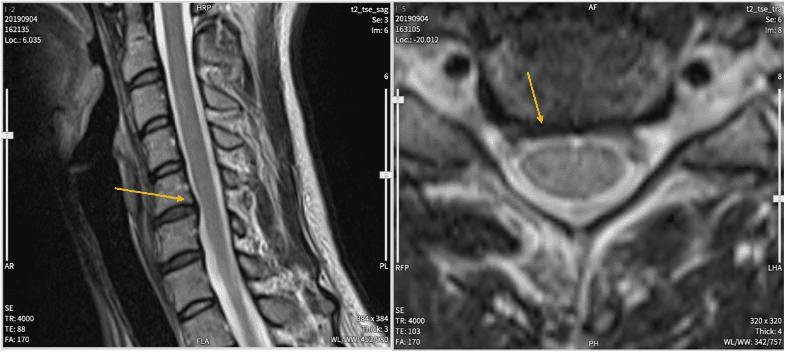

中心性頸髄損傷と交通事故との因果関係(非該当→11級認定)1 依頼内容content事故内容本件事故では、信号待ちのために停車していた被害車両に加害者が被害車両を確認しないまま加害車両を発進させ、被害者が後部座席に乗車し […]